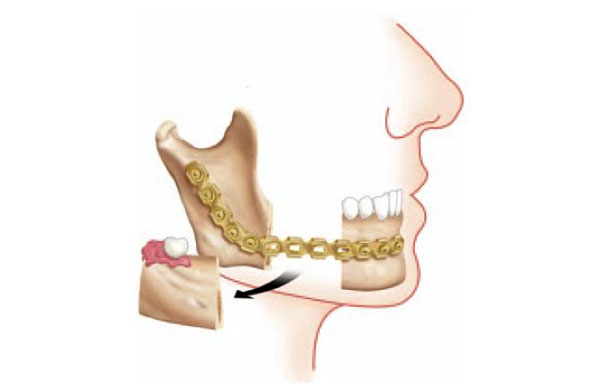

La Cirugía Ortognática se define como la cirugía de corrección de las deformidades dentofaciales que se realiza con la movilización del maxilar superior y la mandíbula en la mayoría de los casos, pudiendo ser combinadas con movilizaciones de mentón entre otros huesos faciales.

Estas intervenciones se practican bajo anestesia general. La corrección de la posición de los maxilares se realiza mediante incisiones intraorales (sin ninguna cicatriz facial). Se efectúa la osteotomía de uno o de los dos maxilares dependiendo de cada caso, y se reponen en la nueva posición fijándose con miniplacas. Esto permite una rápida recuperación de la intervención, con un ingreso hospitalario de uno o dos días, y una reincorporación laboral a los 10 -15 días. Se debe seguir una dieta blanda durante 30-40 días que se inicia el mismo día de la intervención.

- Cirugía Ortognatica para avance maxilar en caso de maloclusión y atrofia.